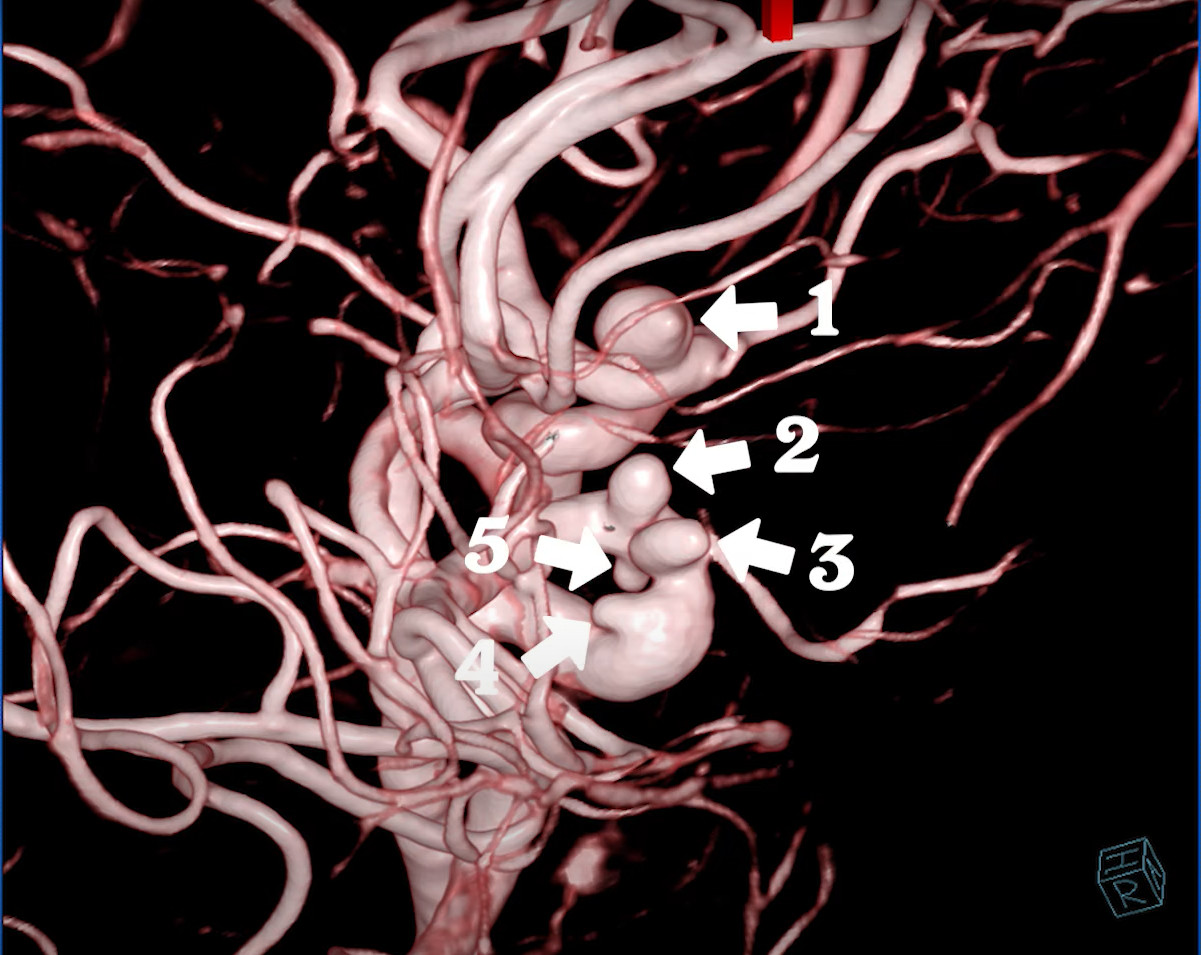

TS.BS Trần Chí Cường trả lời: Trong thời gian vừa qua, chúng ta đã chứng kiến rất nhiều trường hợp đột quỵ ở người trẻ. Có một số trường hợp đột quỵ xảy ra ở cả thiếu niên và học sinh lớp 1, 2. Vừa qua chúng tôi cũng đã điều trị cho 1 trường hợp đột quỵ hiếm gặp, là bệnh nhân nữ 42 tuổi có 5 túi phình mạch máu não. Theo cách nghĩ thông thường, đột quỵ là căn bệnh chỉ xảy ra ở người từ 70 tuổi trở lên có bệnh lý nền như cao huyết áp, mỡ máu cao, hút thuốc nhiều và nghiện rượu bia. Vì vậy, ít khi chúng ta nghĩ tại sao bệnh đột quỵ lại xảy ra ở người trẻ, làm mọi người vô cùng hoang mang và lo sợ. Bên cạnh đó, chúng tôi cũng đã từng cấp cứu cho người bị đột quỵ khoảng 29 tuổi. Sau đó, bệnh nhân tử vong vào ban đêm. Nỗi đau này là sự ngỡ ngàng cho người thân của bệnh nhân, vì không tin người nhà còn trẻ mà có thể bị đột quỵ.

TS.BS Trần Chí Cường trả lời: Đây là trường hợp xảy ra ở bệnh nhân bị một cơn đầu kéo dài và người này đi khám rất nhiều nơi. Một số nơi cho bệnh nhân chụp MRI nhưng chẩn đoán không chính xác, họ chỉ chẩn đoán bệnh nhân bị rối loạn về thần kinh, lo âu, bệnh lý chất trắng. Nhưng khi đến bệnh viện Đa khoa S.I.S Cần Thơ, bệnh nhân được chụp mạch máu não bằng máy cộng hưởng từ MRI 3 Tesla đã phát hiện 5 túi phình mạch máu não và bệnh nhân được điều trị thành công. Lời chia sẻ của bệnh nhân: “Tôi hay bị đau đầu, buồn nôn, hay quên và đứng lên thường bị chóng mặt. Sau một thời gian dài, cơn đau mới giảm xuống và tình trạng này xảy ra thường xuyên. Khi bác sĩ chụp MRI, tôi bị 5 túi phình mạch máu, nên rất lo và hồi hộp vì mạch máu vỡ bất kỳ lúc nào sẽ gây nguy hiểm. Tôi cần sắp xếp để đến bệnh viện vì không biết lúc nào túi phình sẽ vỡ ra. Tôi chưa từng nghĩ tuổi của mình có thể bị bệnh ngặt như vậy. Ngày xưa khi đi khám nhiều nơi, các bác sĩ chẩn đoán bị đau đầu, căng cơ, bị vấn đề dây thần kinh, tôi có đi chụp CT nhưng không tìm ra bệnh, khi chụp MRI mới ra chất trắng. Tôi khuyên các bạn trẻ có dấu hiệu đau đầu không dứt khi dùng thuốc nên đi tầm soát để xem mình có bị phình mạch máu hay không để can thiệp sớm. Đột quỵ không chỉ xảy ra ở người lớn tuổi, mà cả trẻ em cũng bị. Tôi cảm thấy mình may mắn vì đã phát hiện được bệnh gây nguy hiểm như vậy. Tôi cám ơn bệnh viện Đa khoa S.I.S Cần Thơ rất nhiều.”

Kết quả chụp MRI cho thấy 4 túi phình bên phải, 1 túi bên trái